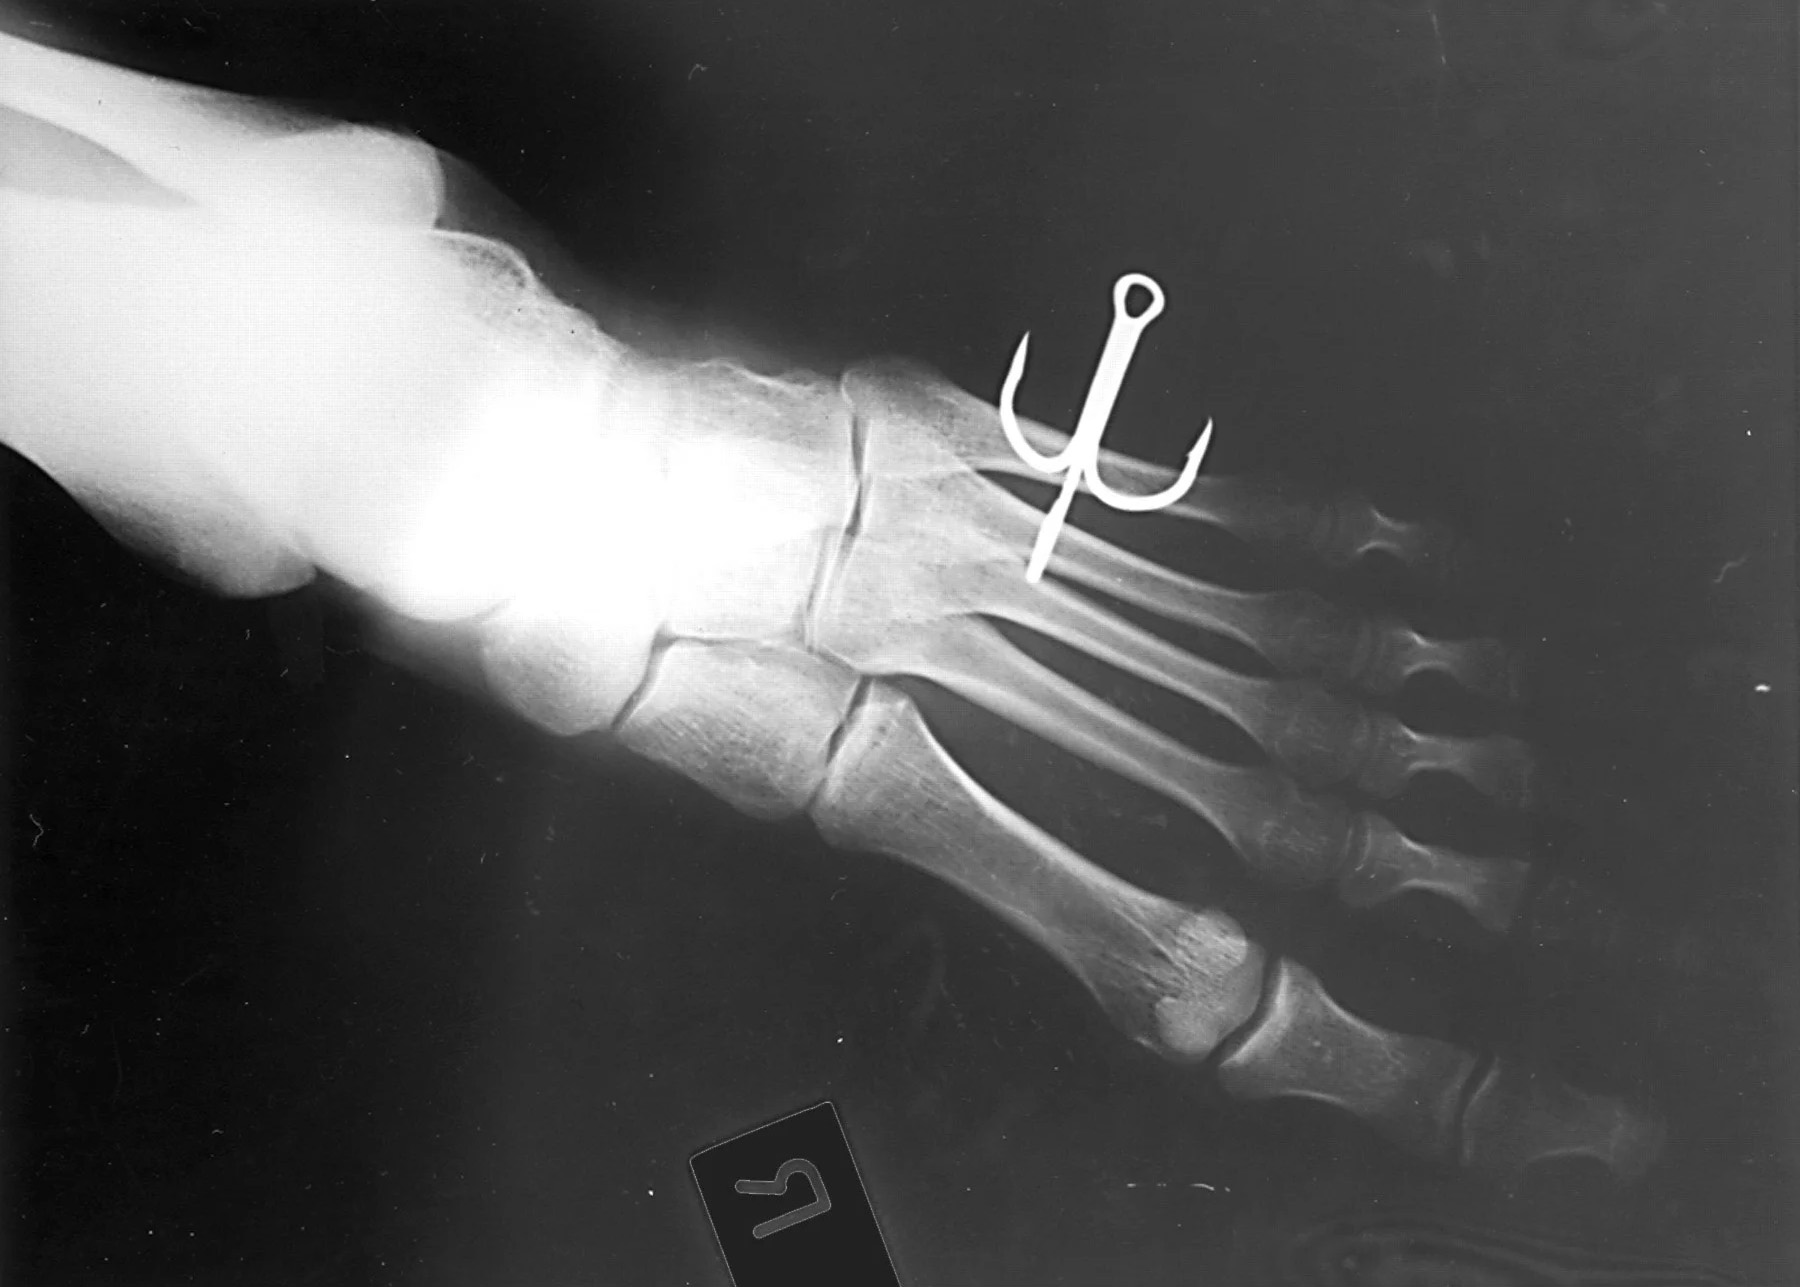

Treble hook

Treble hooks are just the beginning of fishing injuries. British Journal of Sports Medicine

Think this isn’t a real concern? You’re wrong. I’ve seen photos of Texas rig weights embedded in anglers’ cheeks. I’ve seen X-rays of bank sinkers lodged behind eyeballs. I’ve seen the wire arms of bottom-bouncer weights driven into chest plates. Years ago, a man was even killed by a 3-ounce sinker that flew out of the water. And the number of hooks in flesh that got there while freeing a snag are innumerable. The potential for this to occur is one of the reasons why you should always wear sunglasses when you’re fishing, even on overcast days.